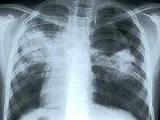

Последние открытие ученых в области воздействия табачного дыма на организм человека, и в частности на его легкие, привели к весьма интересным результатам. Оказывается, в течении длительного курения, легкие изменяются практически таким же образом, как у пациентов с хроническими заболеаниями.

Цель ученых состояла в том, чтобы проанализировать на генетическом уровне образцы легочной ткани у заядлых курильщиков...